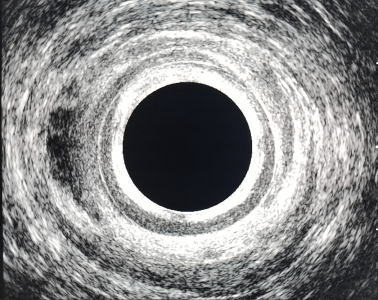

- Görüntüleme yöntemleri (özellikle derin veya karmaşık apselerde):

- Anal ultrason (USG): Apsenin derinliğini ve sfinkterlerle ilişkisini gösterir.